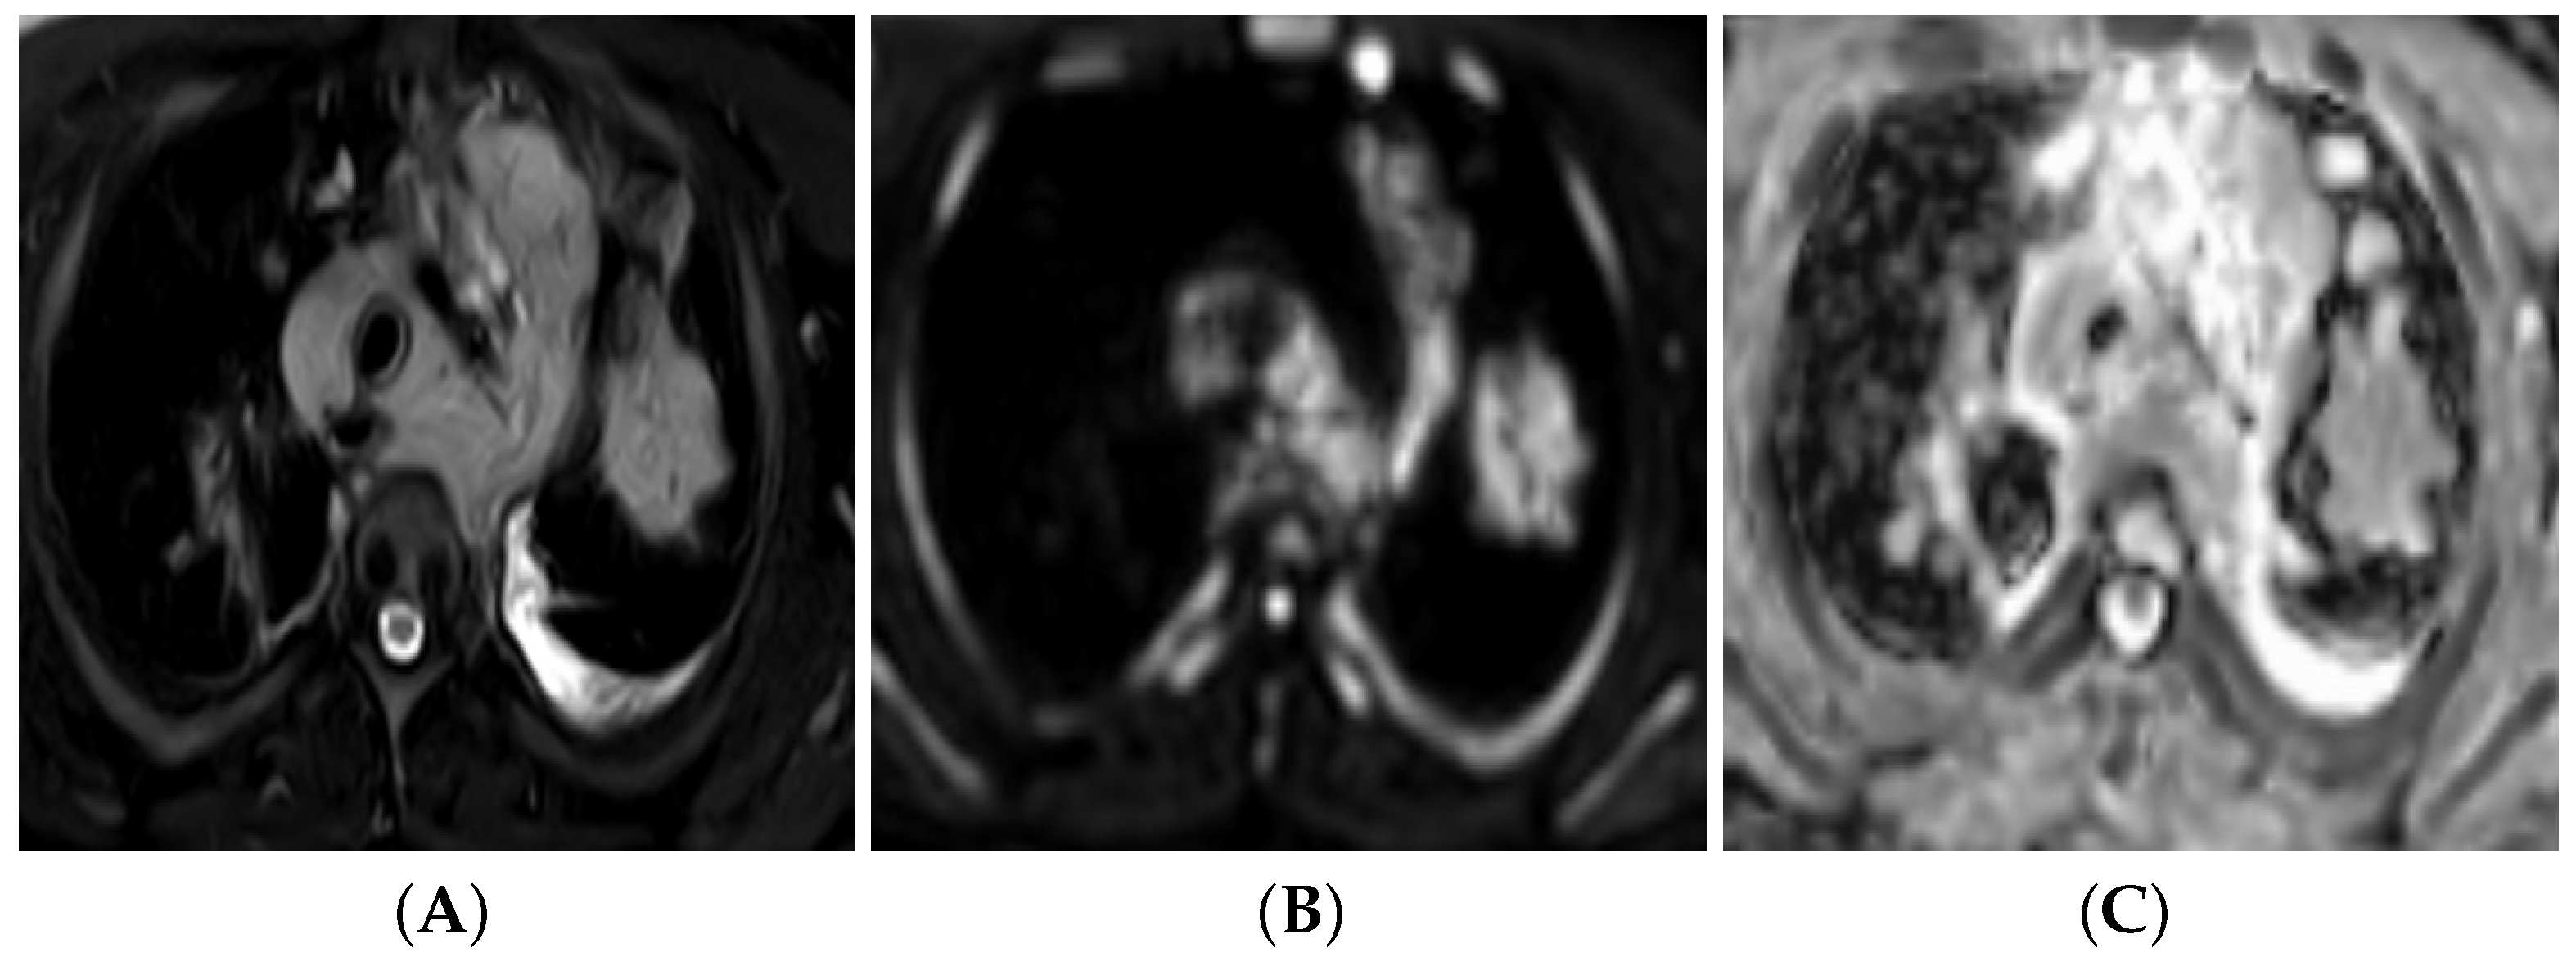

3.6. Diffusion-Weighted Imaging (DWI)

3.6.1. DW Imaging Protocol

3.6.2. Qualitative Image Analysis

3.6.3. Quantitative Image Analysis